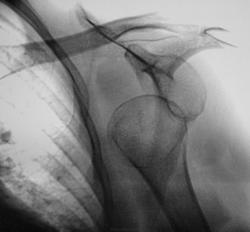

Случай 1

Случай 2.

Случай 3.

Случай 4.

Случай 5.